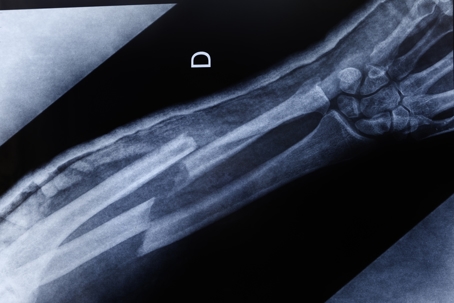

Car accidents can lead to a range of injuries, with broken bones being among the most common. Understanding the different types of fractures can help victims and their families comprehend the severity of these injuries and the road to recovery. Here are six types of broken bones frequently resulting from car accidents.

1. Arm Fractures

Arm fractures, including breaks in the humerus, radius, and ulna, are prevalent in car accidents. These fractures often occur when victims instinctively brace themselves during a collision. This defensive action can result in significant force being applied to the arms, leading to breaks.